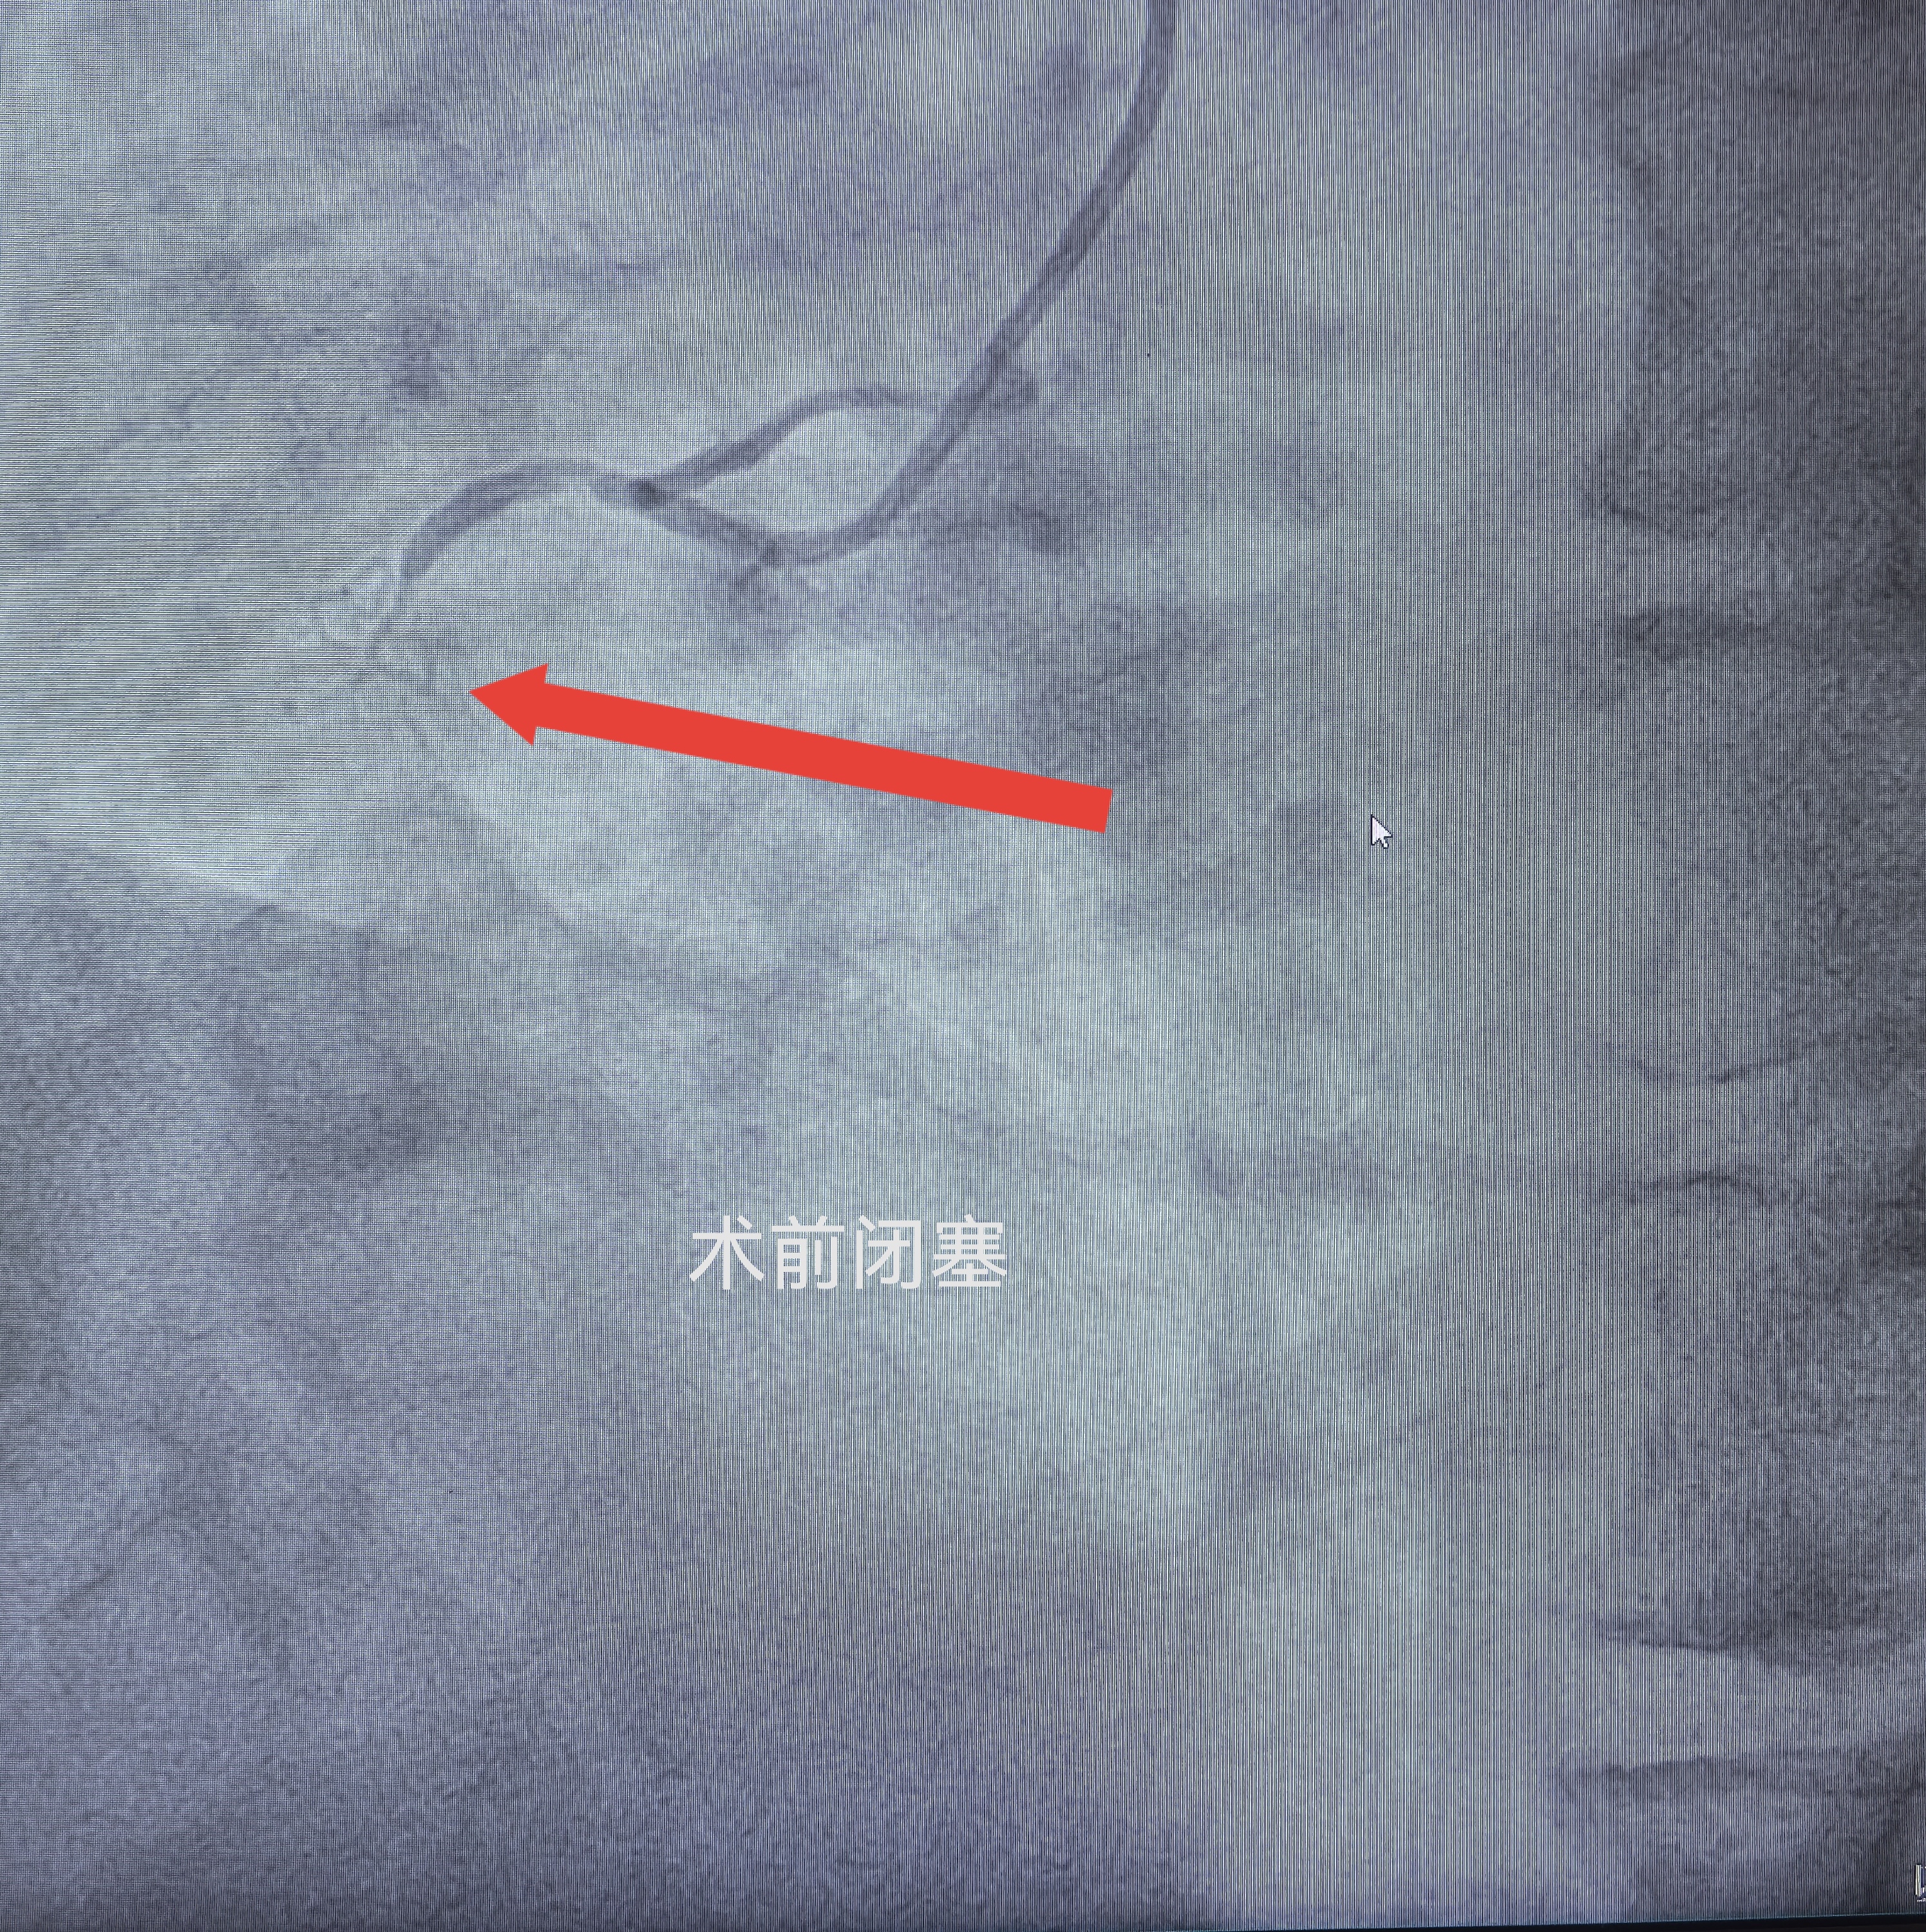

入院后,医疗团队完善各项术前检查,冠脉造影结果明确:患者右冠状动脉慢性完全闭塞,血管钙化程度极为严重,钙化斑块质地坚硬,血管走行复杂,属于冠脉介入领域难度极高的复杂病变。

面对高难度、高风险的复杂手术,科室介入团队严谨研判病情,细致研读影像资料,量身制定个性化手术方案,反复推演术中流程,完备各类应急处置预案,全力保障手术安全开展。术中,团队凝心聚力、默契配合,精准操控介入器械,一点点疏通钙化闭塞血管,顺利完成支架精准植入。术后造影显示,闭塞血管成功疏通,血流通畅,整台手术过程顺利,未发生任何并发症。